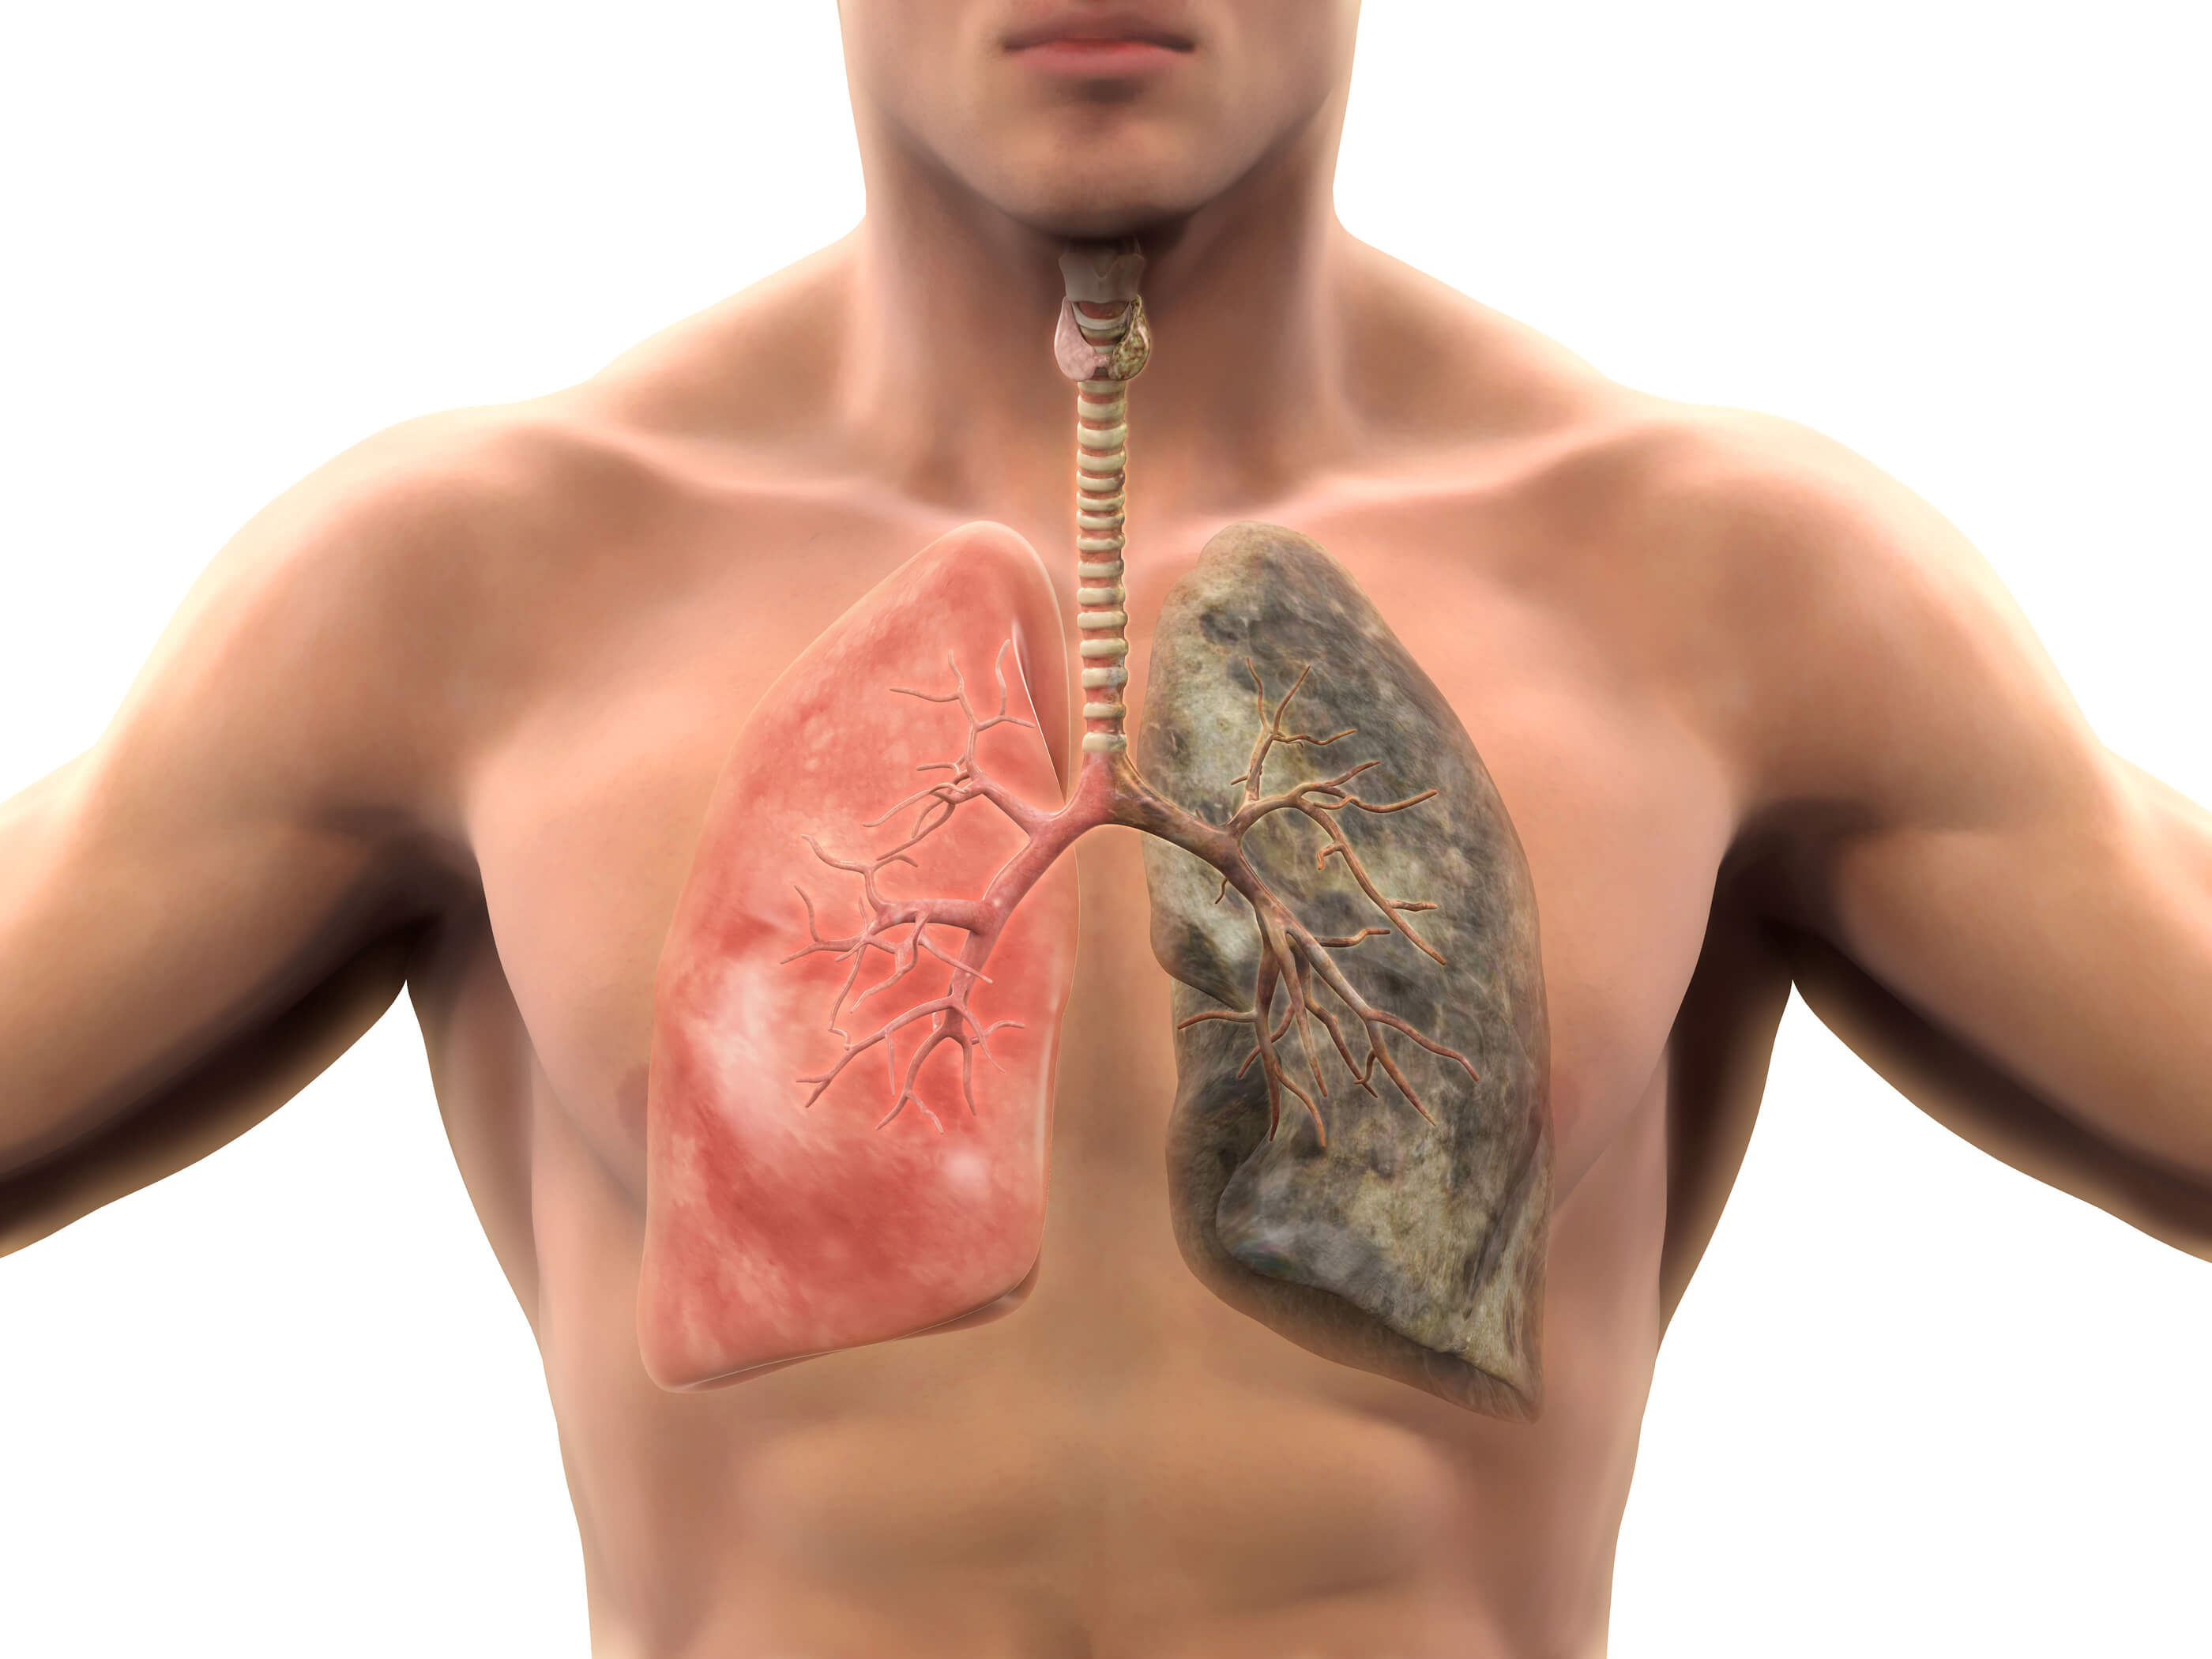

Здоровые Легкие Картинки

Здоровые Легкие Картинки 117 фото